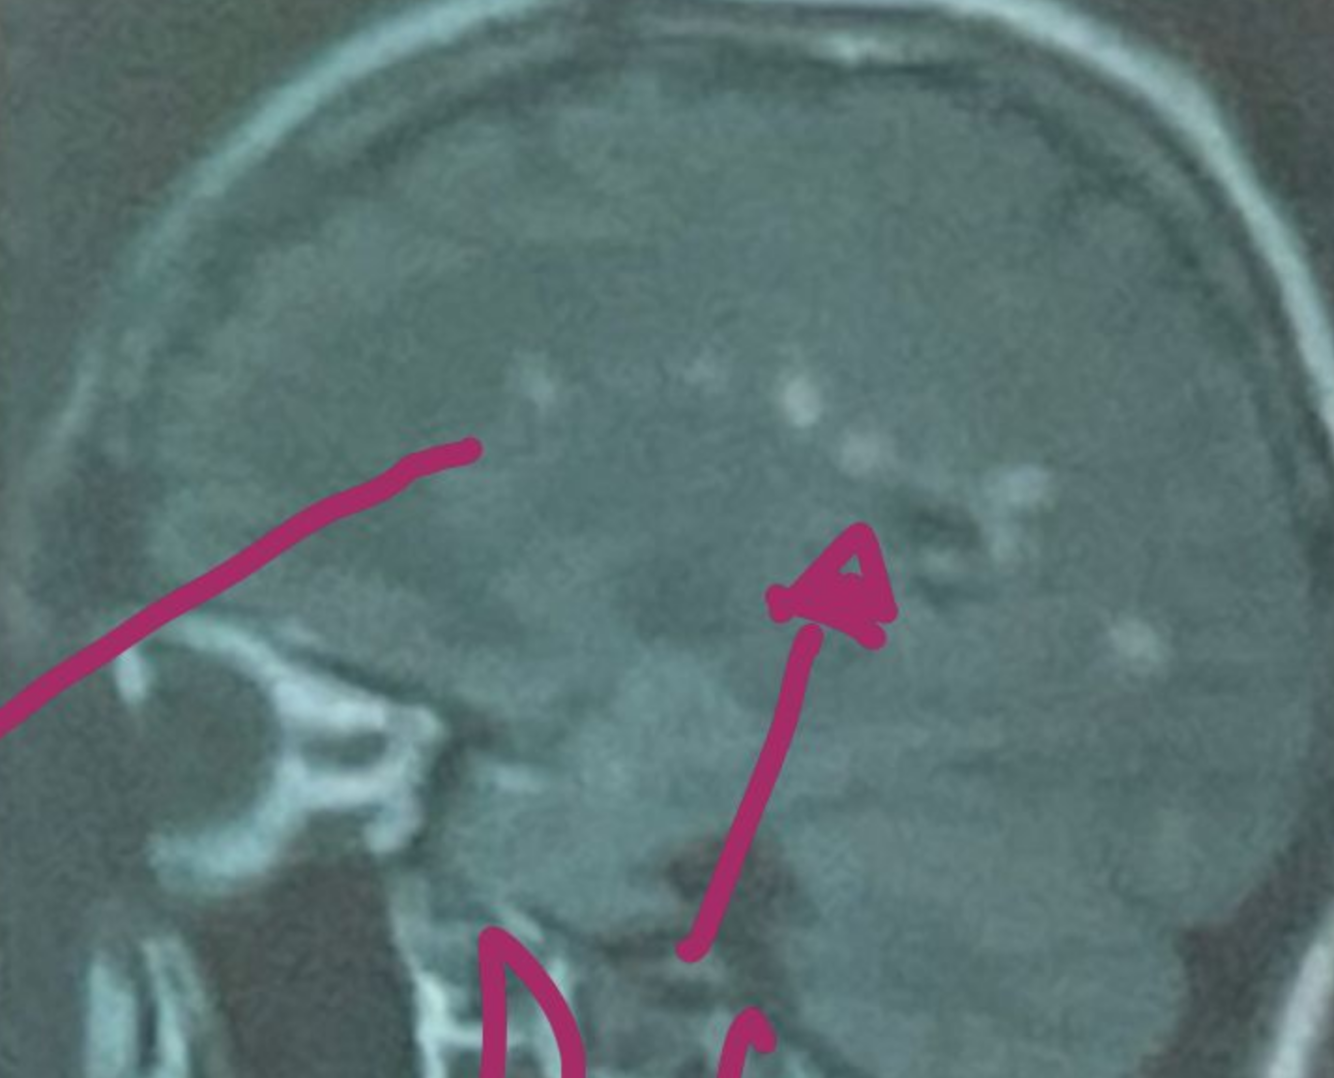

que es esto?

esclerosis multiple

Esta resonancia corresponde a ADEM/EM

EM

En la resonancia magnetica la esclerosis multiple da estos signos:

A

Hiperintensidad en T2 y FLAIR

Hipointensidad en T1

Lesiones redondas y ovaladas, bordes definidos menores a 5mm